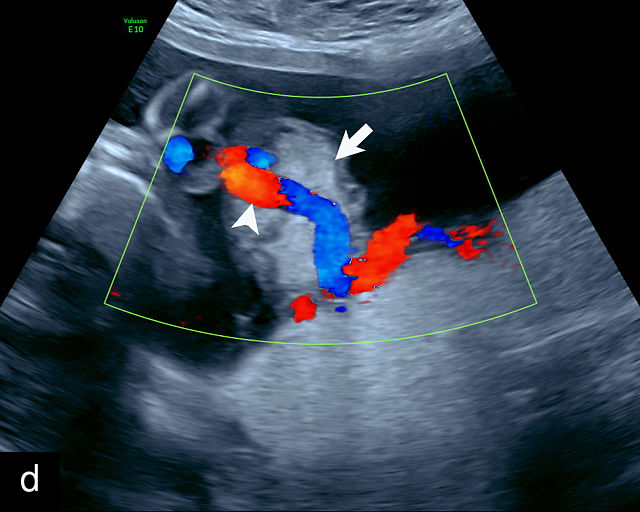

Ultrasound is the primary diagnostic method for identifying VCI. Normally, the cord inserts into the center or edge of the placenta and is fully protected by Wharton’s jelly. In contrast, a velamentous cord insertion is visualized on ultrasound as the cord inserting into the membranes, with unprotected fetal vessels running to the placental margin (Figure 20; Video 11). Color flow Doppler and three-dimensional ultrasound can enhance diagnostic accuracy. Velamentous cord insertion may also occur into the dividing membrane in a multifetal pregnancy (Figure 20e). When unprotected fetal vessels from a VCI cross over the cervix, the condition is termed vasa previa, posing a significant risk of fetal exsanguination if these vessels rupture. Because VCI is a strong risk factor for vasa previa, a color flow Doppler sweep over the cervix is recommended when VCI is identified. If concerns about vasa previa persist, transvaginal ultrasound with color Doppler may be performed for confirmation.30

20

(a–c) Grayscale (a) and color Doppler (b,c) ultrasound images of velamentous cord insertion. The cord inserts into the membranes (arrow), from where unprotected fetal vessels (arrowheads) traverse the membranes to insert into the edge of the anterior (a,b) or posterior (c) placenta (p). (d) Color Doppler ultrasound image of velamentous cord insertion, showing the cord inserting into the membranes posteriorly (arrow), from where unprotected fetal vessels (arrowheads) traverse the membranes to insert into the edge of the anterior placenta (p). (e) Ultrasound with color Doppler showing velamentous vessels (arrow) running through the dividing membrane in a dichorionic diamniotic twin pregnancy. The right image shows the placenta after delivery.